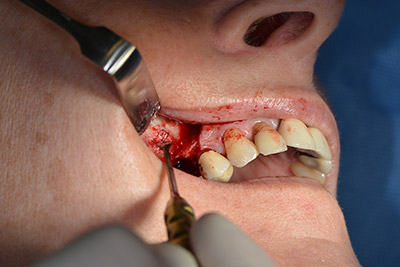

Acto seguido, se coloca el implante y se estructura el hueso. Dado el tamaño del aumento, en el caso que nos ocupa se utilizó hueso autógeno, que había surgido como virutas de fresado en el implante 16 y en la fenestración 14 y se había recogido con un colector óseo, y se combinó con material de reemplazo óseo.

Una membrana reabsorbible formó la barrera en sentido bucal y cubrió el aumento. Por último se procedió a la sutura de modo que no penetrara saliva (figuras 15 a 19).

Aumento con hueso autógeno

Imagen 15

Imagen 16

Implantología

Imagen 17

Imagen 18

cierre de la herida para que no penetre saliva

Imagen 19